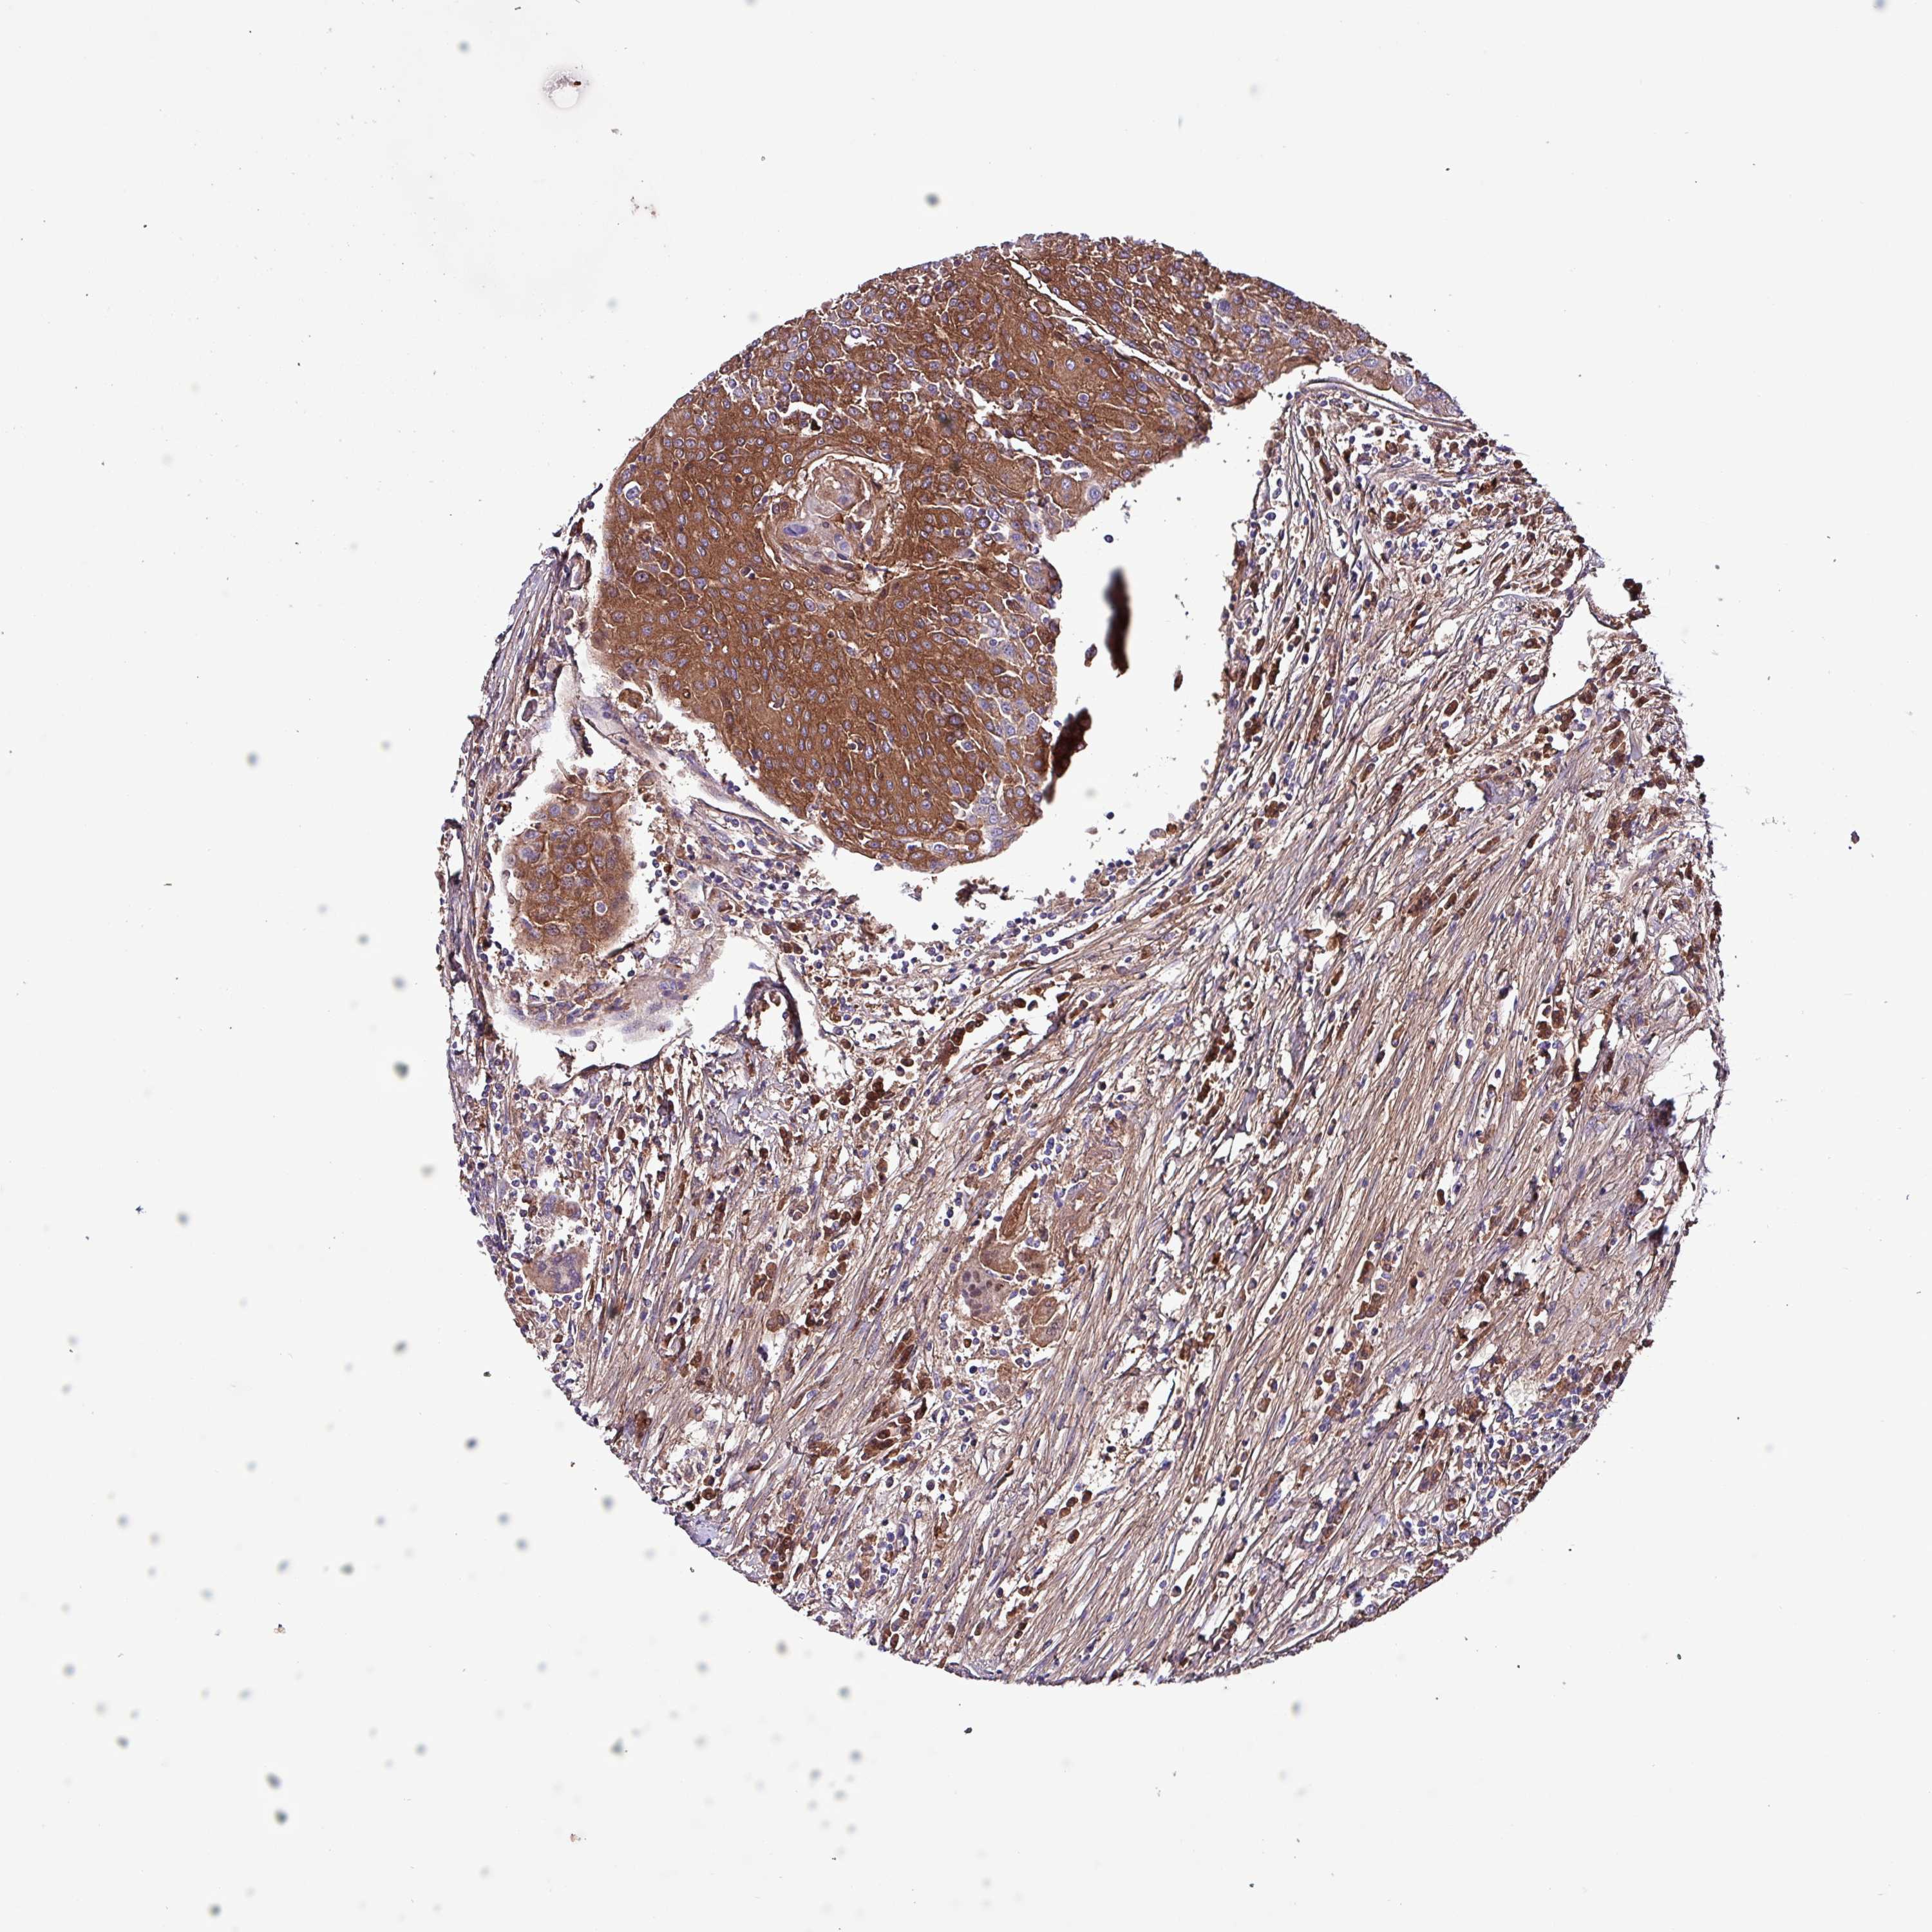

UROTHELIAL CANCER - Protein expressioni

A mouse-over function shows sample information and annotation data. Click on an image to view it in a full screen mode. Samples can be filtered based on level of antibody staining by selecting one or several of the following categories: high, medium, low and not detected. The assay and annotation is described here.

Note that samples used for immunohistochemistry by the Human Protein Atlas do not correspond to samples in the TCGA dataset.

Antibody stainingi

Antibody staining in the annotated cell types in the current human tissue is reported as not detected, low, medium, or high, based on conventional immunohistochemistry profiling in selected tissues. This score is based on the combination of the staining intensity and fraction of stained cells.

Each image is clickable and will lead to virtual microscopy that enables deeper exploration of all samples and also displays staining intensity scores, fraction scores and subcellular localization as well as patient and tissue information for each sample.

Antibody HPA047750

Staining

High

Medium

Low

Not detected

Intensity

Strong

Moderate

Weak

Negative

Quantity

>75%

75%-25%

<25%

None

Location

Nuclear

Cytoplasmic/membranous

Cytoplasmic/membranous,nuclear

Urothelial carcinoma, High grade

Urothelial carcinoma, NOS

Urothelial carcinoma, Low grade